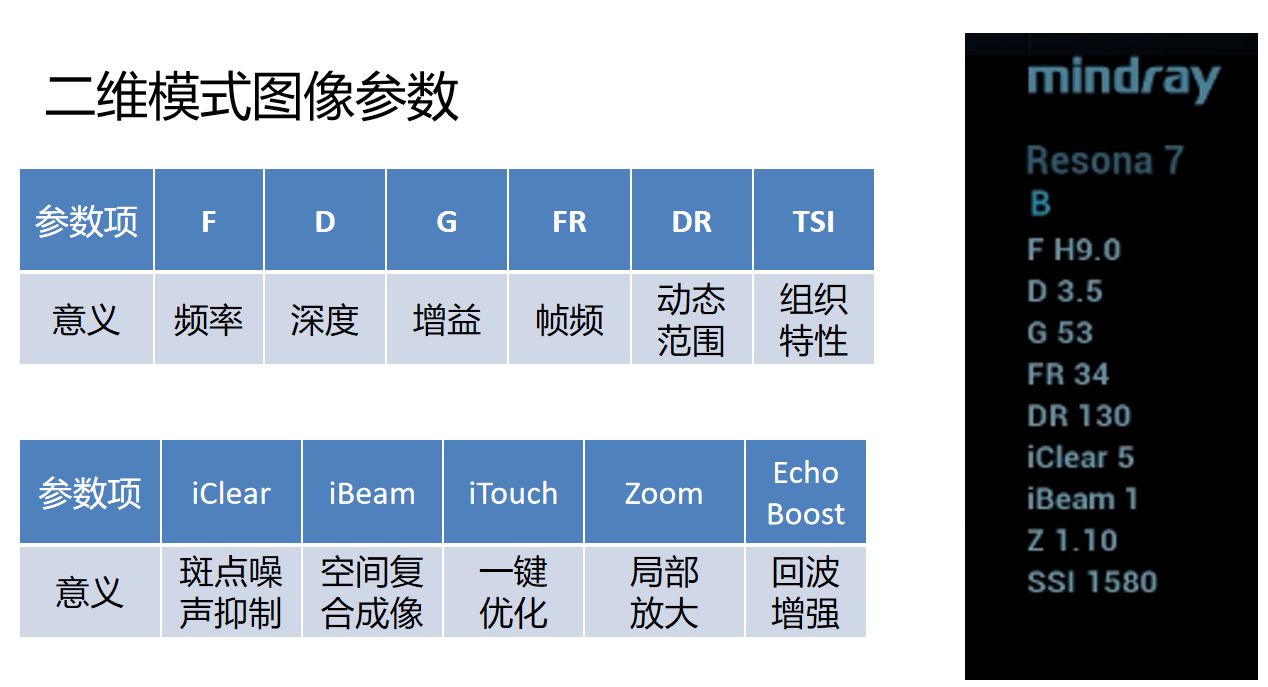

在介绍辉阶二维图像(B模式图像)参数调节之前我们先了解一下各个参数。以迈瑞高端彩超RE7为例,最上面的Resona7代表机器型号,B是代表二维模式,F代表的是频率,后面这个H代表谐波,9.0是频率的意思。

我们知道图像调节的重要性后,来了解一下辉阶二维图像参数调节都包括:探头及预设条件的选择,频率的调整,谐波的开关,深度/视野调节,总增益/深度增益补偿和动态范围的调节等等。